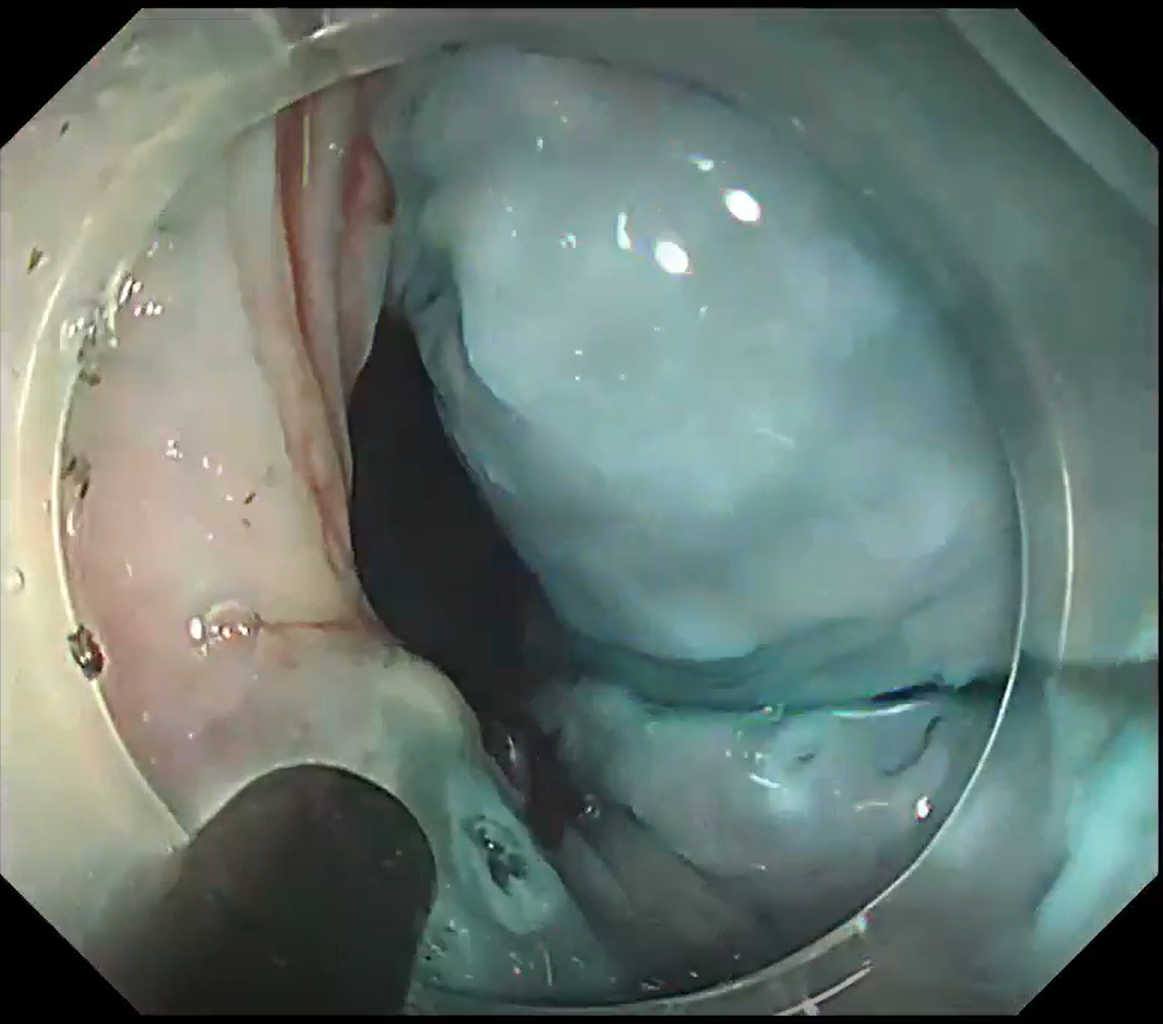

This case involved a 0-IIc lesion on the posterior wall of the mid thoracic esophagus, adjacent to a post ESD scar. Submucosal lifting was insufficient despite hyaluronic-acid injection (Figs. 9 & 10). Using an ultra-sharp DualKnife in this situation carries a measurable perforation risk and increases operator anxiety. Instead, a “push-through mucosal incision” with the small insulated tip of ITknife nano was chosen (Movie 2).

After lifting on the oral side of the scar, the tip was advanced and a blunt, controlled mucosal cut was made (Figs. 11 & 12). Once a full circumferential incision was complete, the remainder of the dissection was finished quickly and safely with the ITknife nano blade, achieving en-bloc resection in a short time.